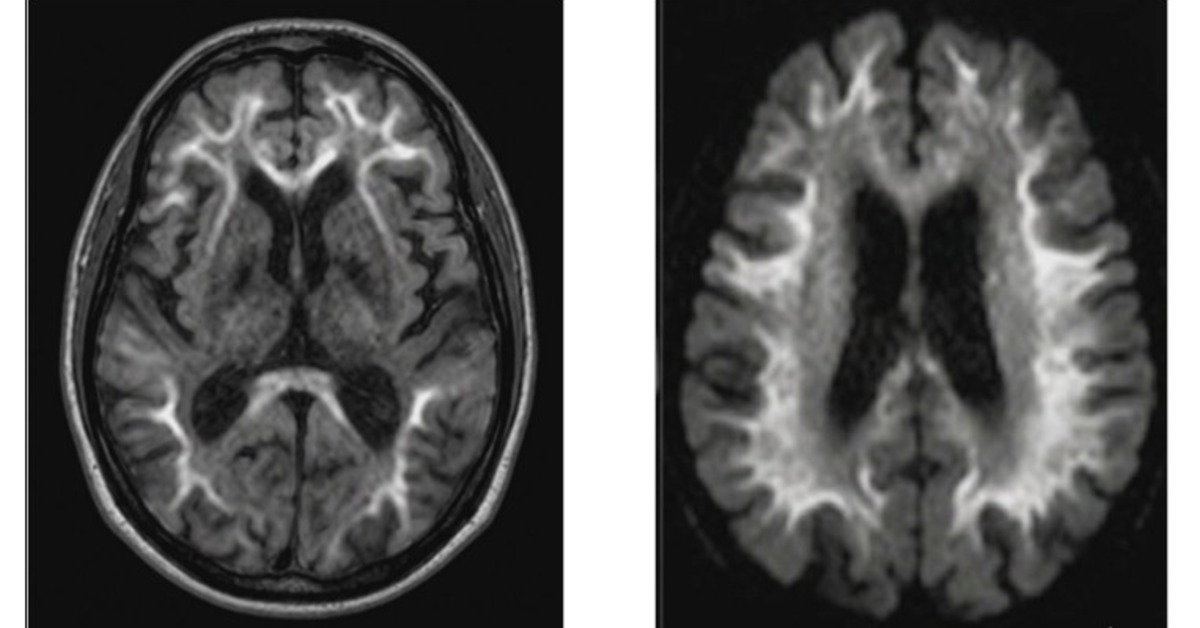

大腦皮髓質交界處對稱性高訊號曲線。(圖/陳珮昀醫師提供)

醫療團隊在核磁共振(MRI)的 DWI 序列下,觀察到阿嬤的腦部出現了極其特殊的特徵在「皮質髓質交界處」出現了對稱的高訊號曲線。陳珮昀醫師指出,這種影像特徵就像是「疾病的指紋」,高度指向近年醫界才逐漸重視的罕病NIID。